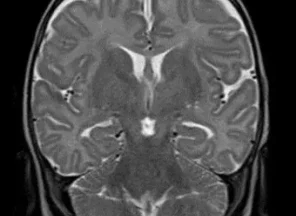

Иссечение дермальных синусов, дермоидных кист и перикраниальных синусовРазличают краниальный и спинальный дермальный синусы. Дермальный синус может заканчиваться как в мягких тканях, так и проникать в полость черепа или позвоночного канала. В последних случаях имеется высокий риск развития менингита. Лечение только хирургическое, проводится полное иссечение синуса. При распространении синуса до твердой мозговой оболочки свищ иссекается вместе с окружающим участком твердой мозговой оболочки. Дефект твердой мозговой оболочки герметично ушивается.